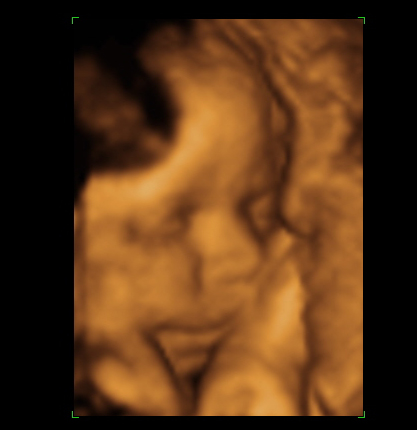

Akkora élmény volt a 4d, őrület:D olyan széééép, pont olyan dundifejű, mint amilyet szerettem volna :D

És már befordult.:-) hurrrááá

1514 gramm (27 hetesen 1057,3 volt)

és marad a február 15

kicsit meszes a méhlepény, de semmi extra. lehet a sok kólától, úgyhogy most visszaveszek. Az egyik veséje kicsit tágabb, de azt mondta a nőci, hogy pánikra semmi ok, nagyon sok fiúnál van ez, hol az egyik tágultabb hol a másik, és aggódni csak sokkal nagyobbnál kell. hát remélem is.... de nem aggódom meglepő módon ezen.